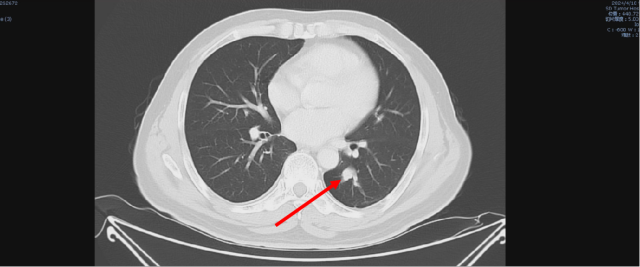

舒尼替尼治疗后,2023-05-09 复查 CT

1. 结合临床,左肾癌术后;考虑肝转移,较前(2023-02-06)增大。

2. 双肺多发结节,较前变化不著。

3. 前列腺钙化灶;盆腔少量积液,较前减少。

4. L5 双侧椎弓崩解;L2 椎体致密灶,变化不著,观察。